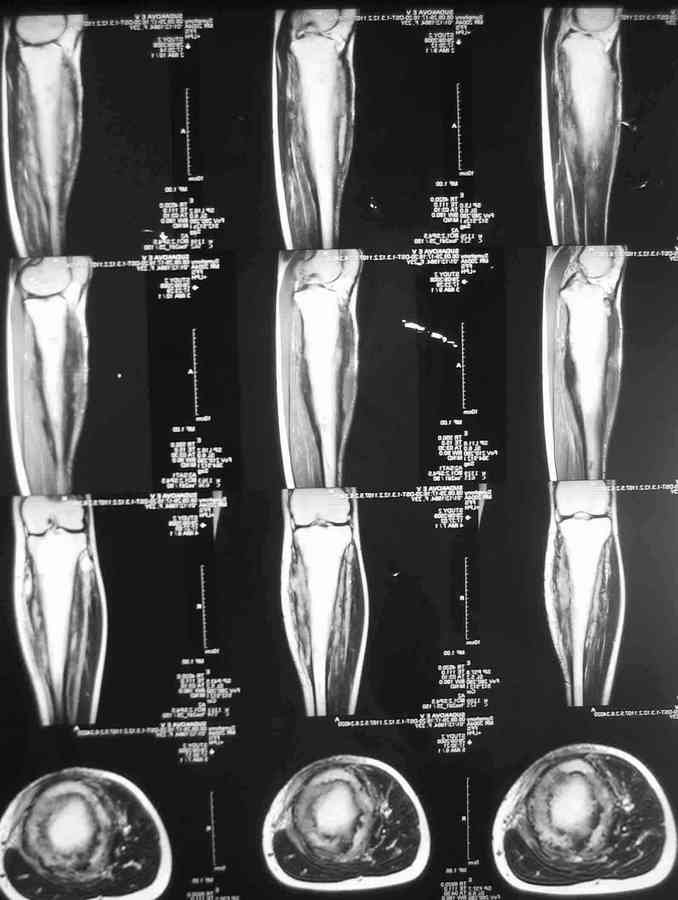

Остеомиелит Гарре

Господа, обратилась девушка 20 с небольшим лет.Больна с 2002 года. остеомиелит Гарре. Подтвержден гистологически.

Чем можно помочь? Кто этим занимается серьезно? И вообще какие подходы в лечении?С уважением Александр Артемьев